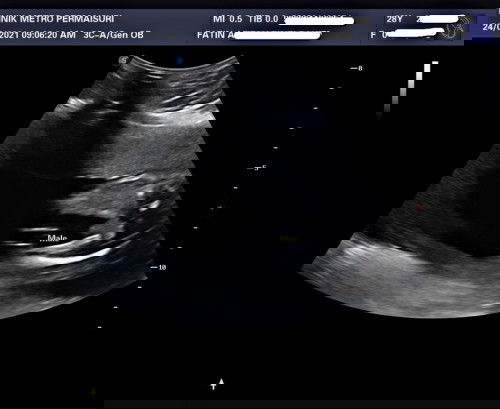

GENDER BABY BOY OR GIRL?

Hi mommies, nak tanya scan ni sure ke nampak baby boy ya? Sy baru buat detail scan semalam. Nak make sure utk mommies yg dah ada experience since ni my first baby. Is it really pistol? 😅 takut je beli baju boy then keluar nanti girl, tapi sy beli jg baju unisex before tau gender dia. TQ in advance! #pleasehelp #1stimemom #firstbaby #boyorgirl